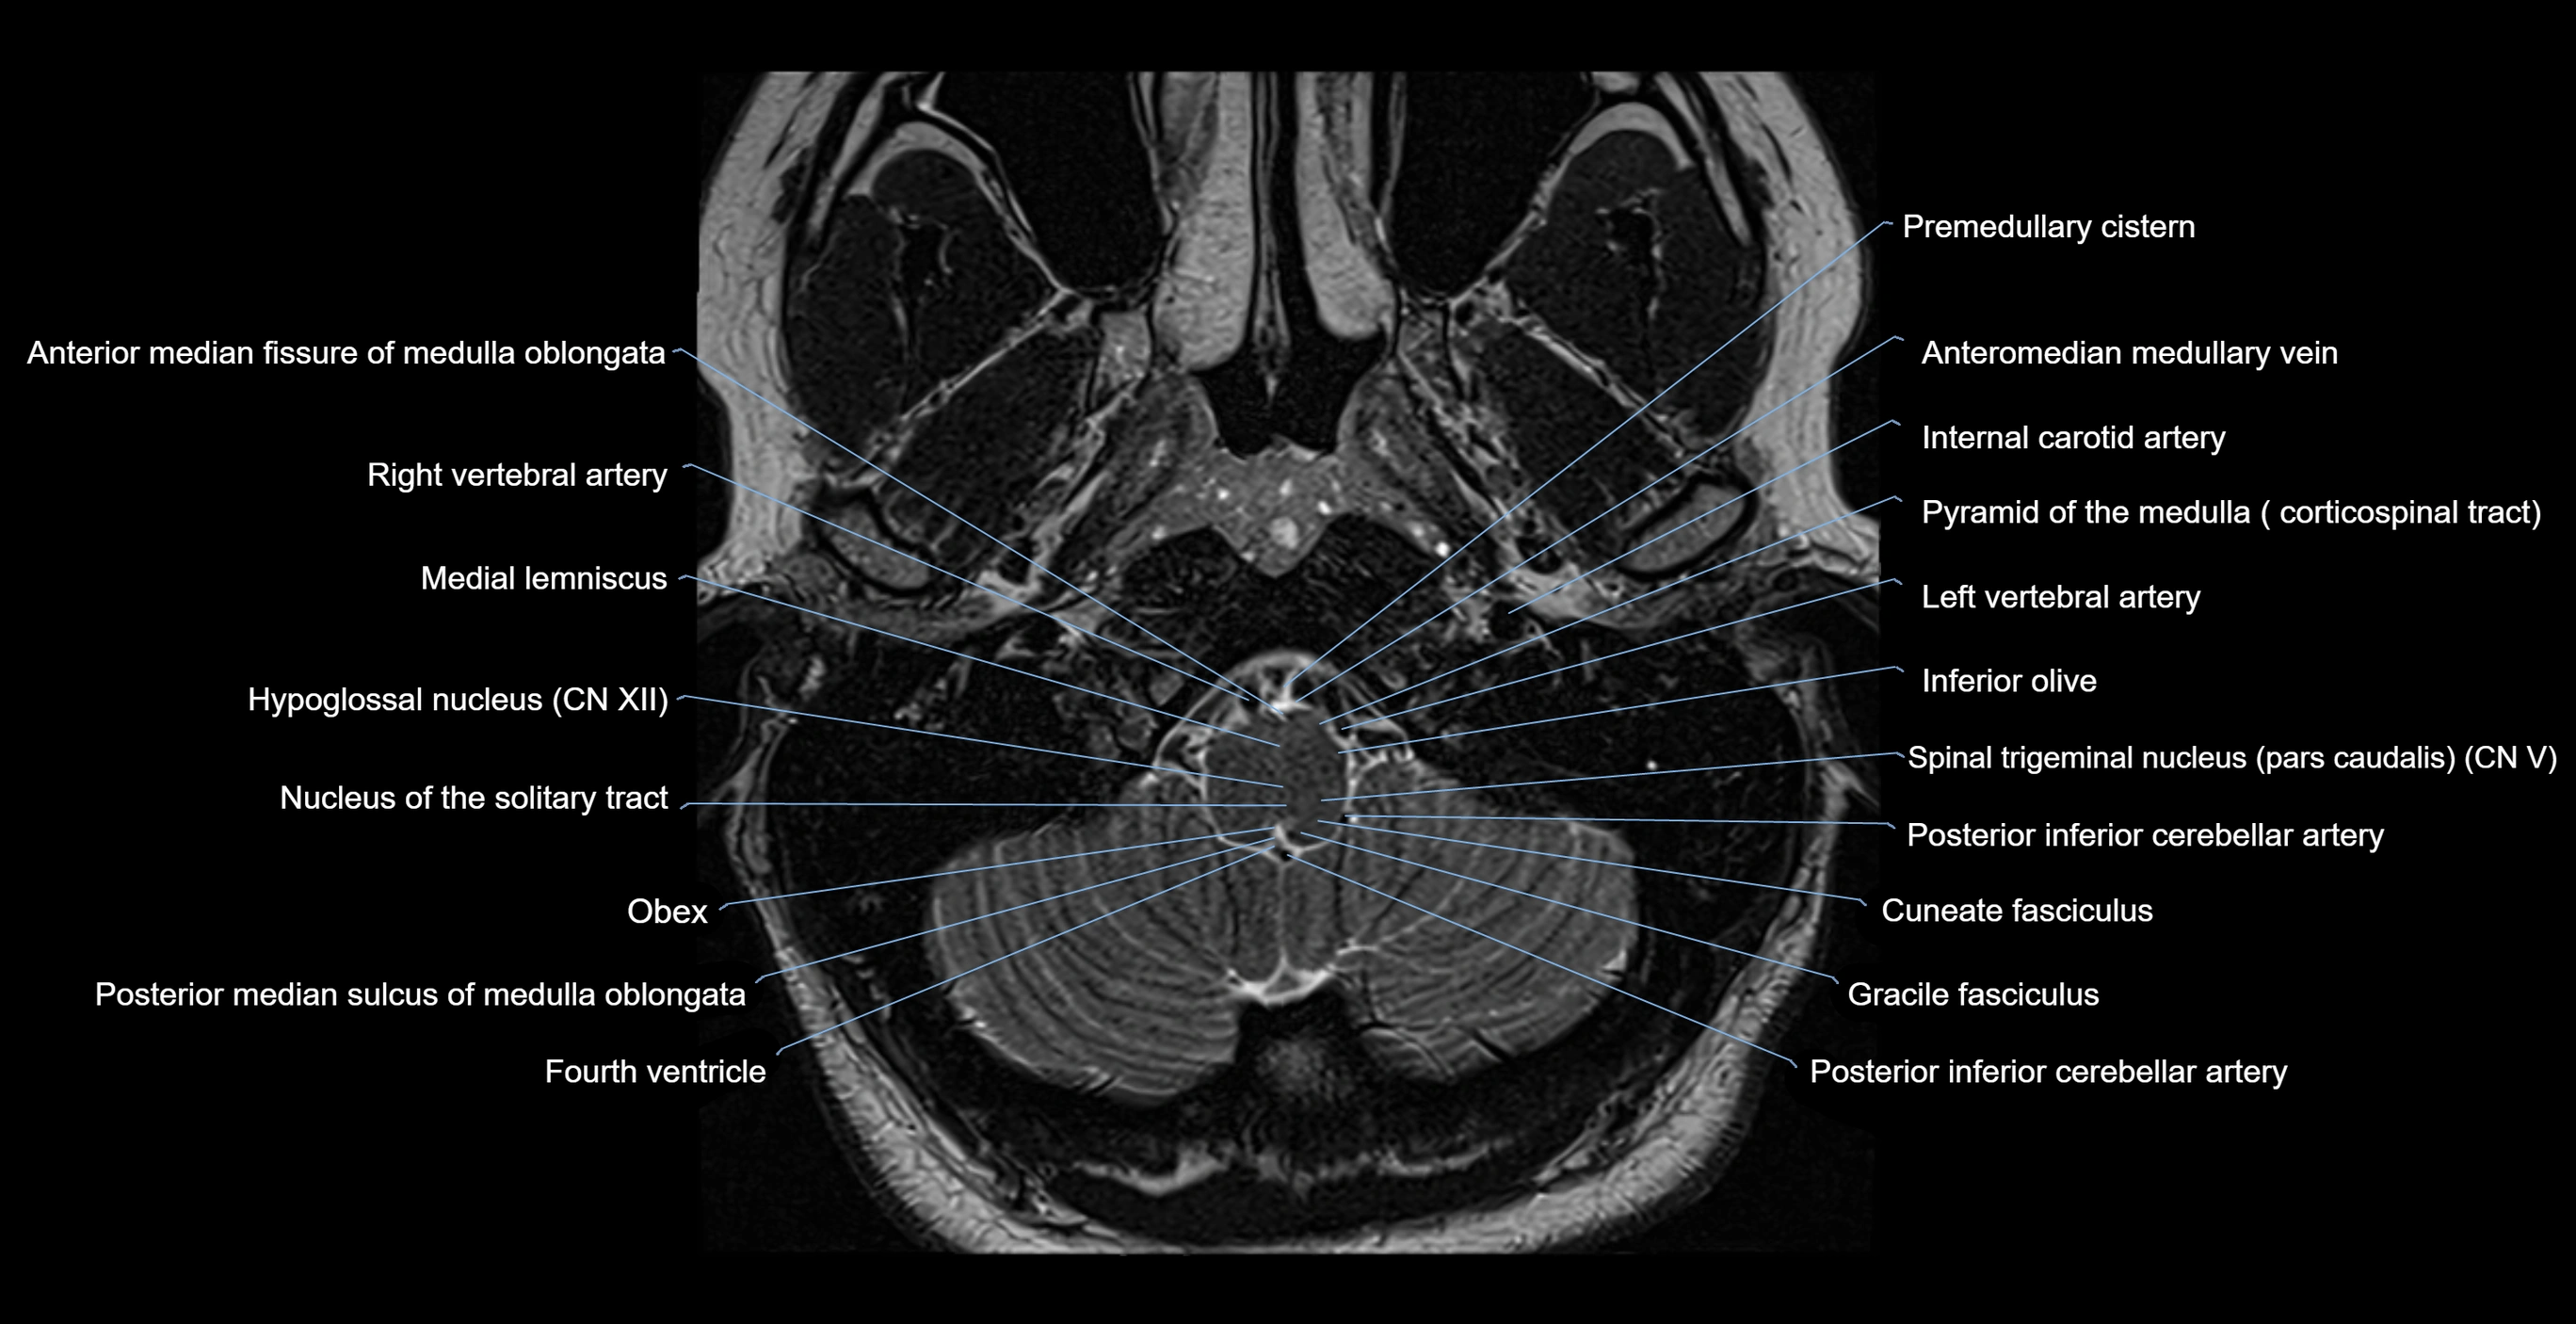

MRI images